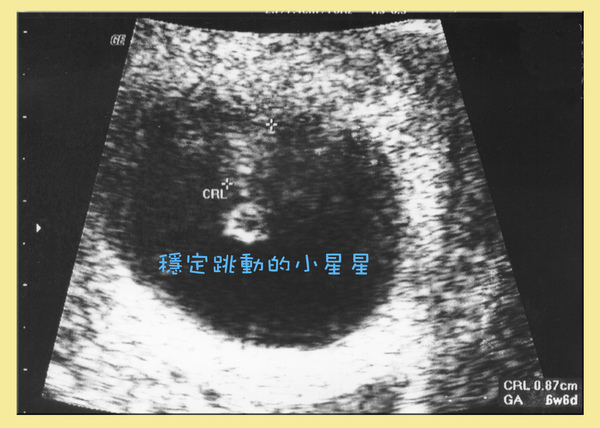

簡單的問診之後,李醫師就幫我照超音波,

他說:「六週又六天,小Baby已經有心跳了!今天可以領媽媽手冊囉!」

看著螢幕上,ㄚ寶已經不是小湯圓了,

一閃一閃的小星星是ㄚ寶的心跳耶!{#emotions_dlg.emotion_043}